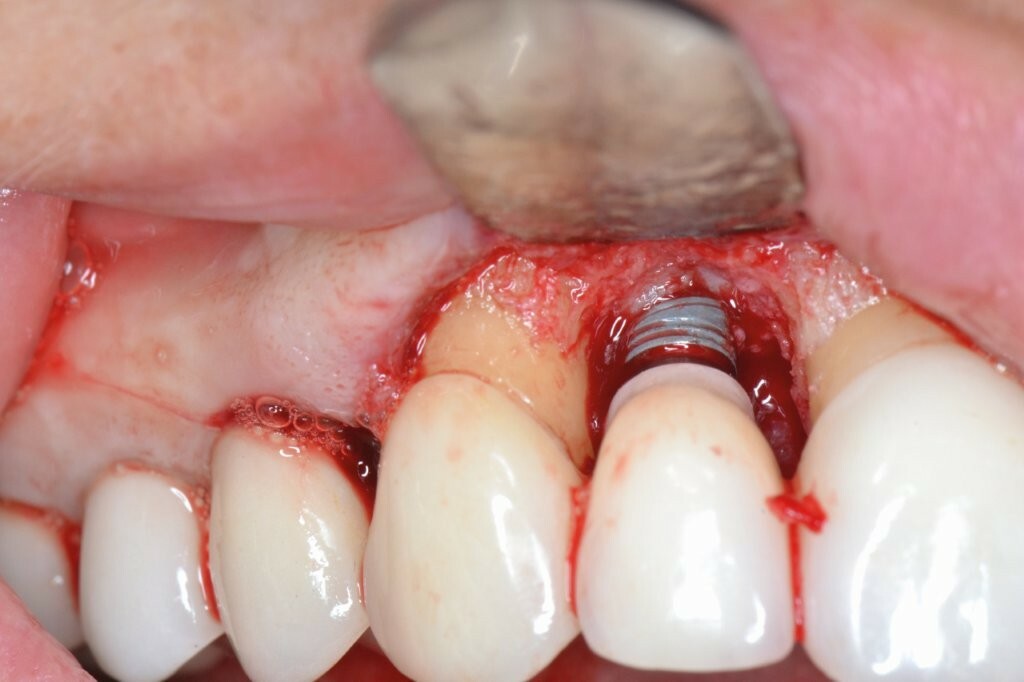

Ein Minilappen wurde sowohl bukkal als auch palatinal am Implantat unter Einbeziehung der beiden Nachbarzähne gebildet. Das entzündete Gewebe wurde kürettiert, wobei wir einen 3 mm großen horizontalen Defekt mit einem stärkeren Knochenverlust auf der bukkalen Seite feststellten. Gemäß des zuvor beschriebenen Protokolls erfolgten zwei aufeinanderfolgende 5-minütige Anwendungen von OXYSAFE-Gel. Der Defekt wurde vorsichtig mit einem Xenotransplantat aufgefüllt und mit einem Kollagenvlies abgedeckt, der Lappen anschließend koronal mit einer Kopfnaht vernäht.